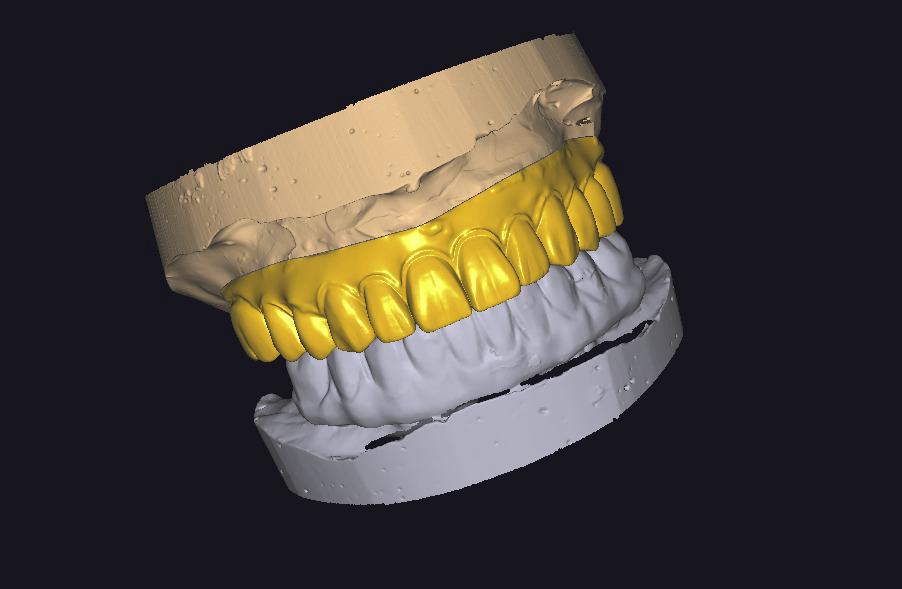

HYBRID PROTEZLER

HYBRID CAM CAM CrCo & TITANYUM PORSELEN BITIM

HYBRID CAM CAM CrCo ARA cOvDE PORSELEN BITIM

HYBRID CAM CAM CrCo TiTANYUM BiTIMSIZ KRON

HYBRID cam cam CrCo BITIMSIZ KRON ARA GOVDE

HYBRID CAM CAM CrCo KOMPOZIT BiTiM

HYBRID CAM CAM CrCo ARA Oyu KOMPOZIT BITIM

HYBRID CAM CAM CrCo TITANYUM ARA GÖVDE PORSELEN BİTİM

VIDALI IMPLANT USTU BAR (HER ABUTMENT BAŞI)